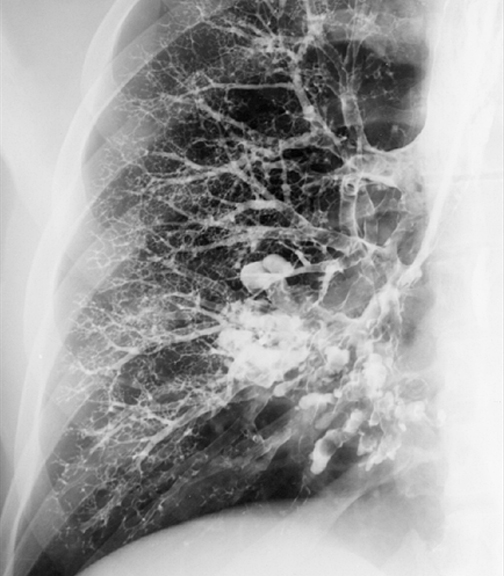

Gallery Bronchiectasis Bronchiectasis Case 3 PA bronchogram

Case 3 PA bronchogram